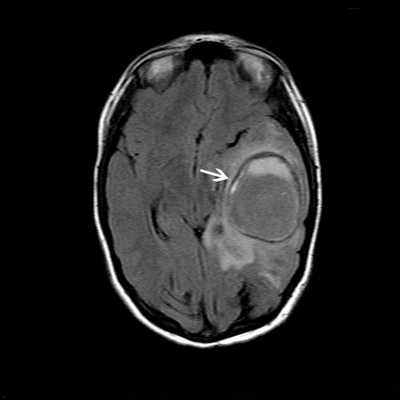

МРТ головного мозга. Резко ограниченная овальная масса левой височной и теменной доли (отогенный абсцесс головного мозга, белая стрелка) после недавней операции на левом среднем ухе.